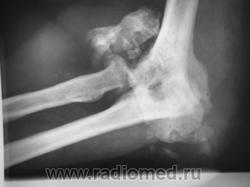

КСС. Артропатия. Сирингомиелия. +

Артропатия.  Сирингомиелия.